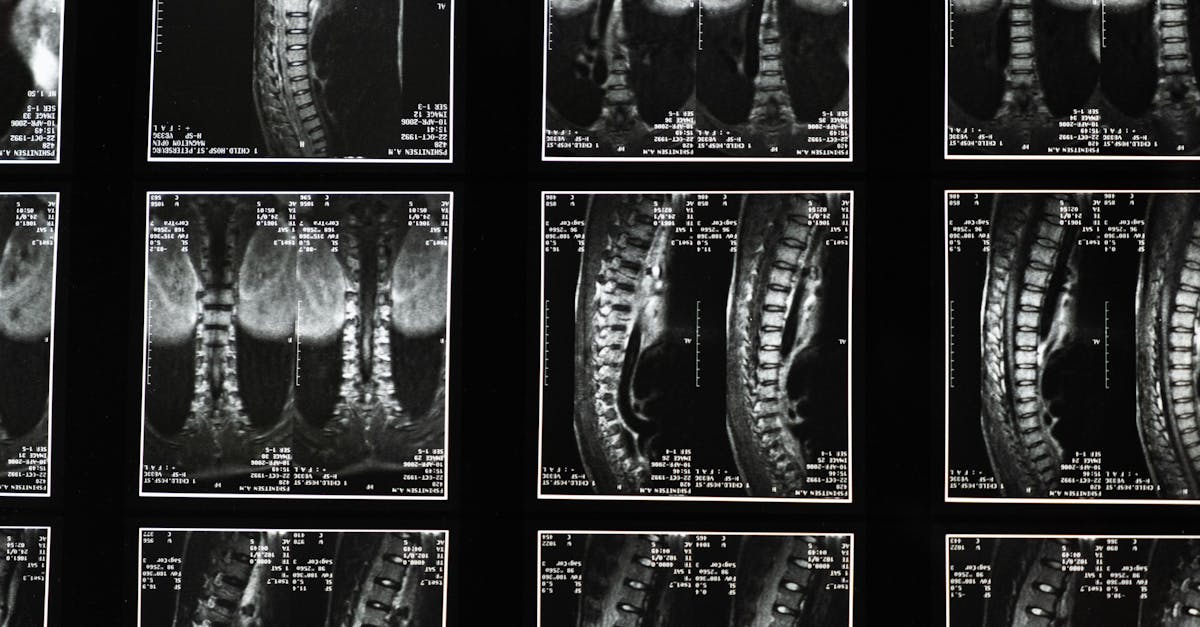

Scoliosis is a condition characterized by an abnormal curvature of the spine, often leading to challenges in daily movement and overall comfort. Fortunately, incorporating effective posture exercises can greatly improve your experience. In this article, we will explore essential scoliosis exercises and highlight how working with Pulse Align can facilitate your journey toward better posture and neuromuscular health.